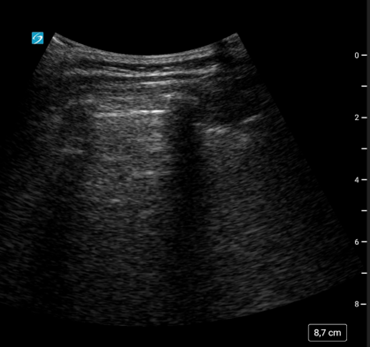

Realizamos una ecografía clínica en la que vemos líneas A en todos los campos pulmonares izquierdos. Sin embargo, en los derechos, observamos abundantes líneas B, especialmente en campos medios y una imagen de consolidación del parénquima pulmonar.